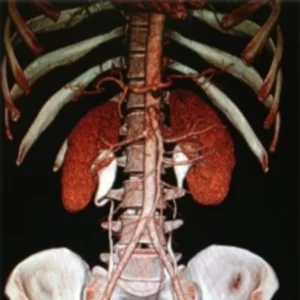

CT Angiogram

Normal kidney position

The kidneys lie retroperitoneally (behind the peritoneum) in the abdomen, either side of the vertebral column. They typically extend from T12 to L3, although the right kidney is often situated slightly lower due to the presence of the liver. Each kidney is approximately three vertebrae in length.